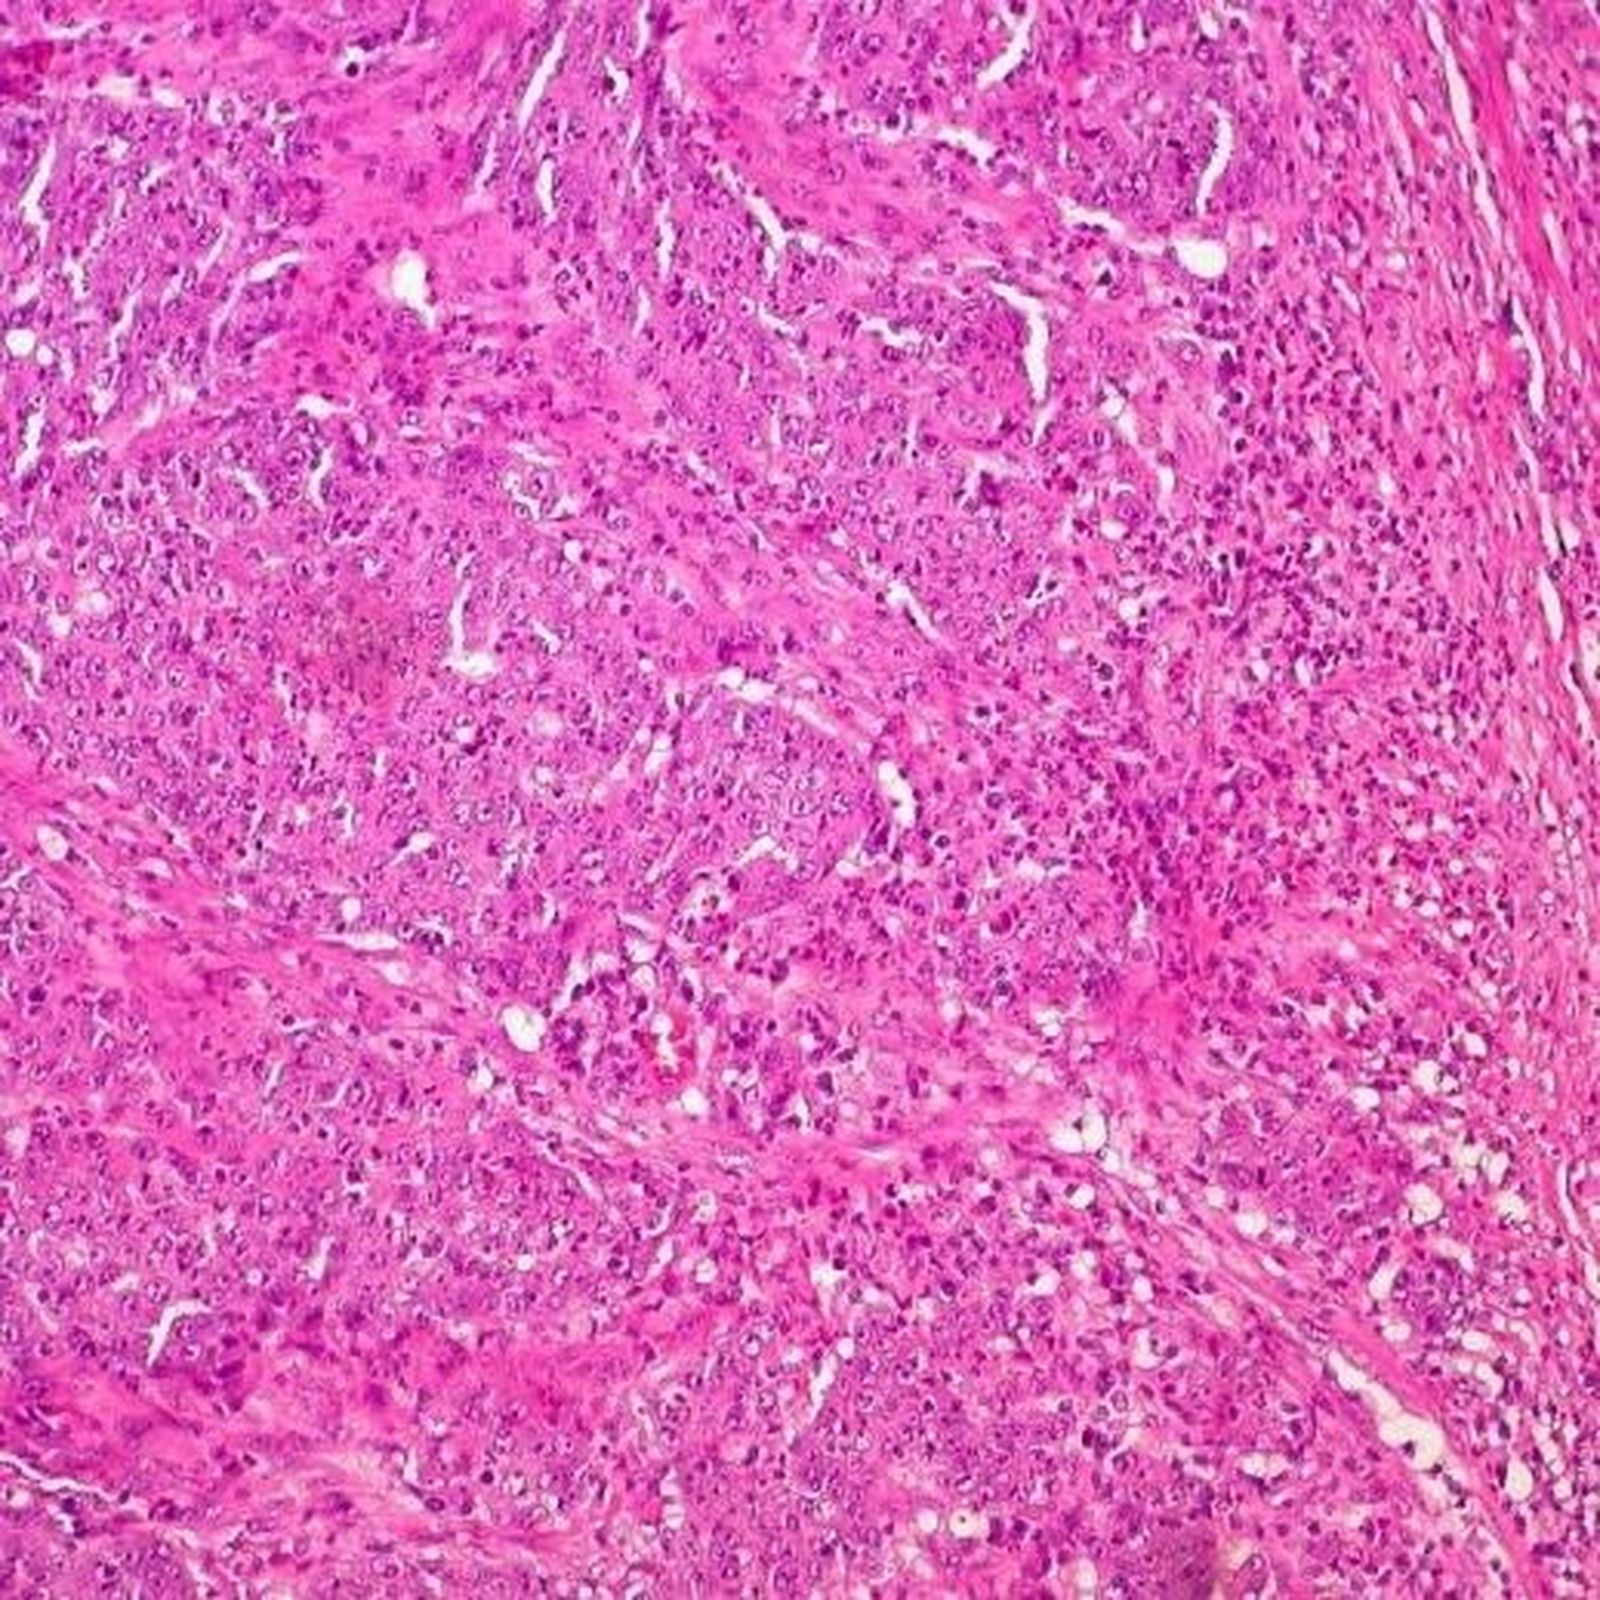

Hasta ahora, numerosos estudios epidemiológicos han demostrado la asociación de la deficiencia en vitamina D con una mayor incidencia y mortalidad de diversos cánceres, como es el caso del cáncer colorrectal (CRC). La alteración de estas células troncales ("madre" o stem) es crucial en el inicio, progresión y resistencia al tratamiento del CRC. Los investigadores describen la acción del calcitriol en la células frenando la proliferación e induciendo la diferenciación de las células stem cancerosas (Cancer Stem Cells).

Los resultados indican que el calcitriol inhibe la proliferación e invasividad y promueve la diferenciación de las células de carcinoma de colon. Además, los datos recientes muestran un efecto protector de la vitamina D actuando sobre los fibroblastos estromales aislados de pacientes con este tipo de cáncer. Los resultados ahora publicados muestran un efecto protector adicional frente al CRC actuando sobre las 'Stem Cells'".